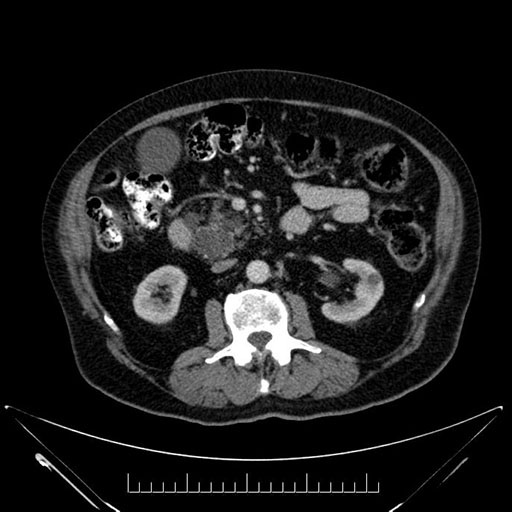

Imaging Analysis

Look through the patient's CT scan to identify any areas of concern for the necessary procedure.

Based on your CT findings, which issue(s) would give reason for "planned slowing down moment(s)" in this case?

Considering a standard Whipple procedure, what step(s) of the operation would you do differently in this case?